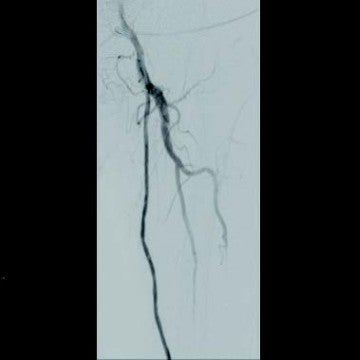

[背景] 左間欠性跛行で14年前に左SFAにベアナイチノールステント6 mm × 120 mm 2本が留置されている(図1)。約7年前に左間欠性跛行が増悪し、来院。外来での超音波検査でベアステントの完全閉塞を認めた(図2)。高度の跛行があり、再治療を実施した。